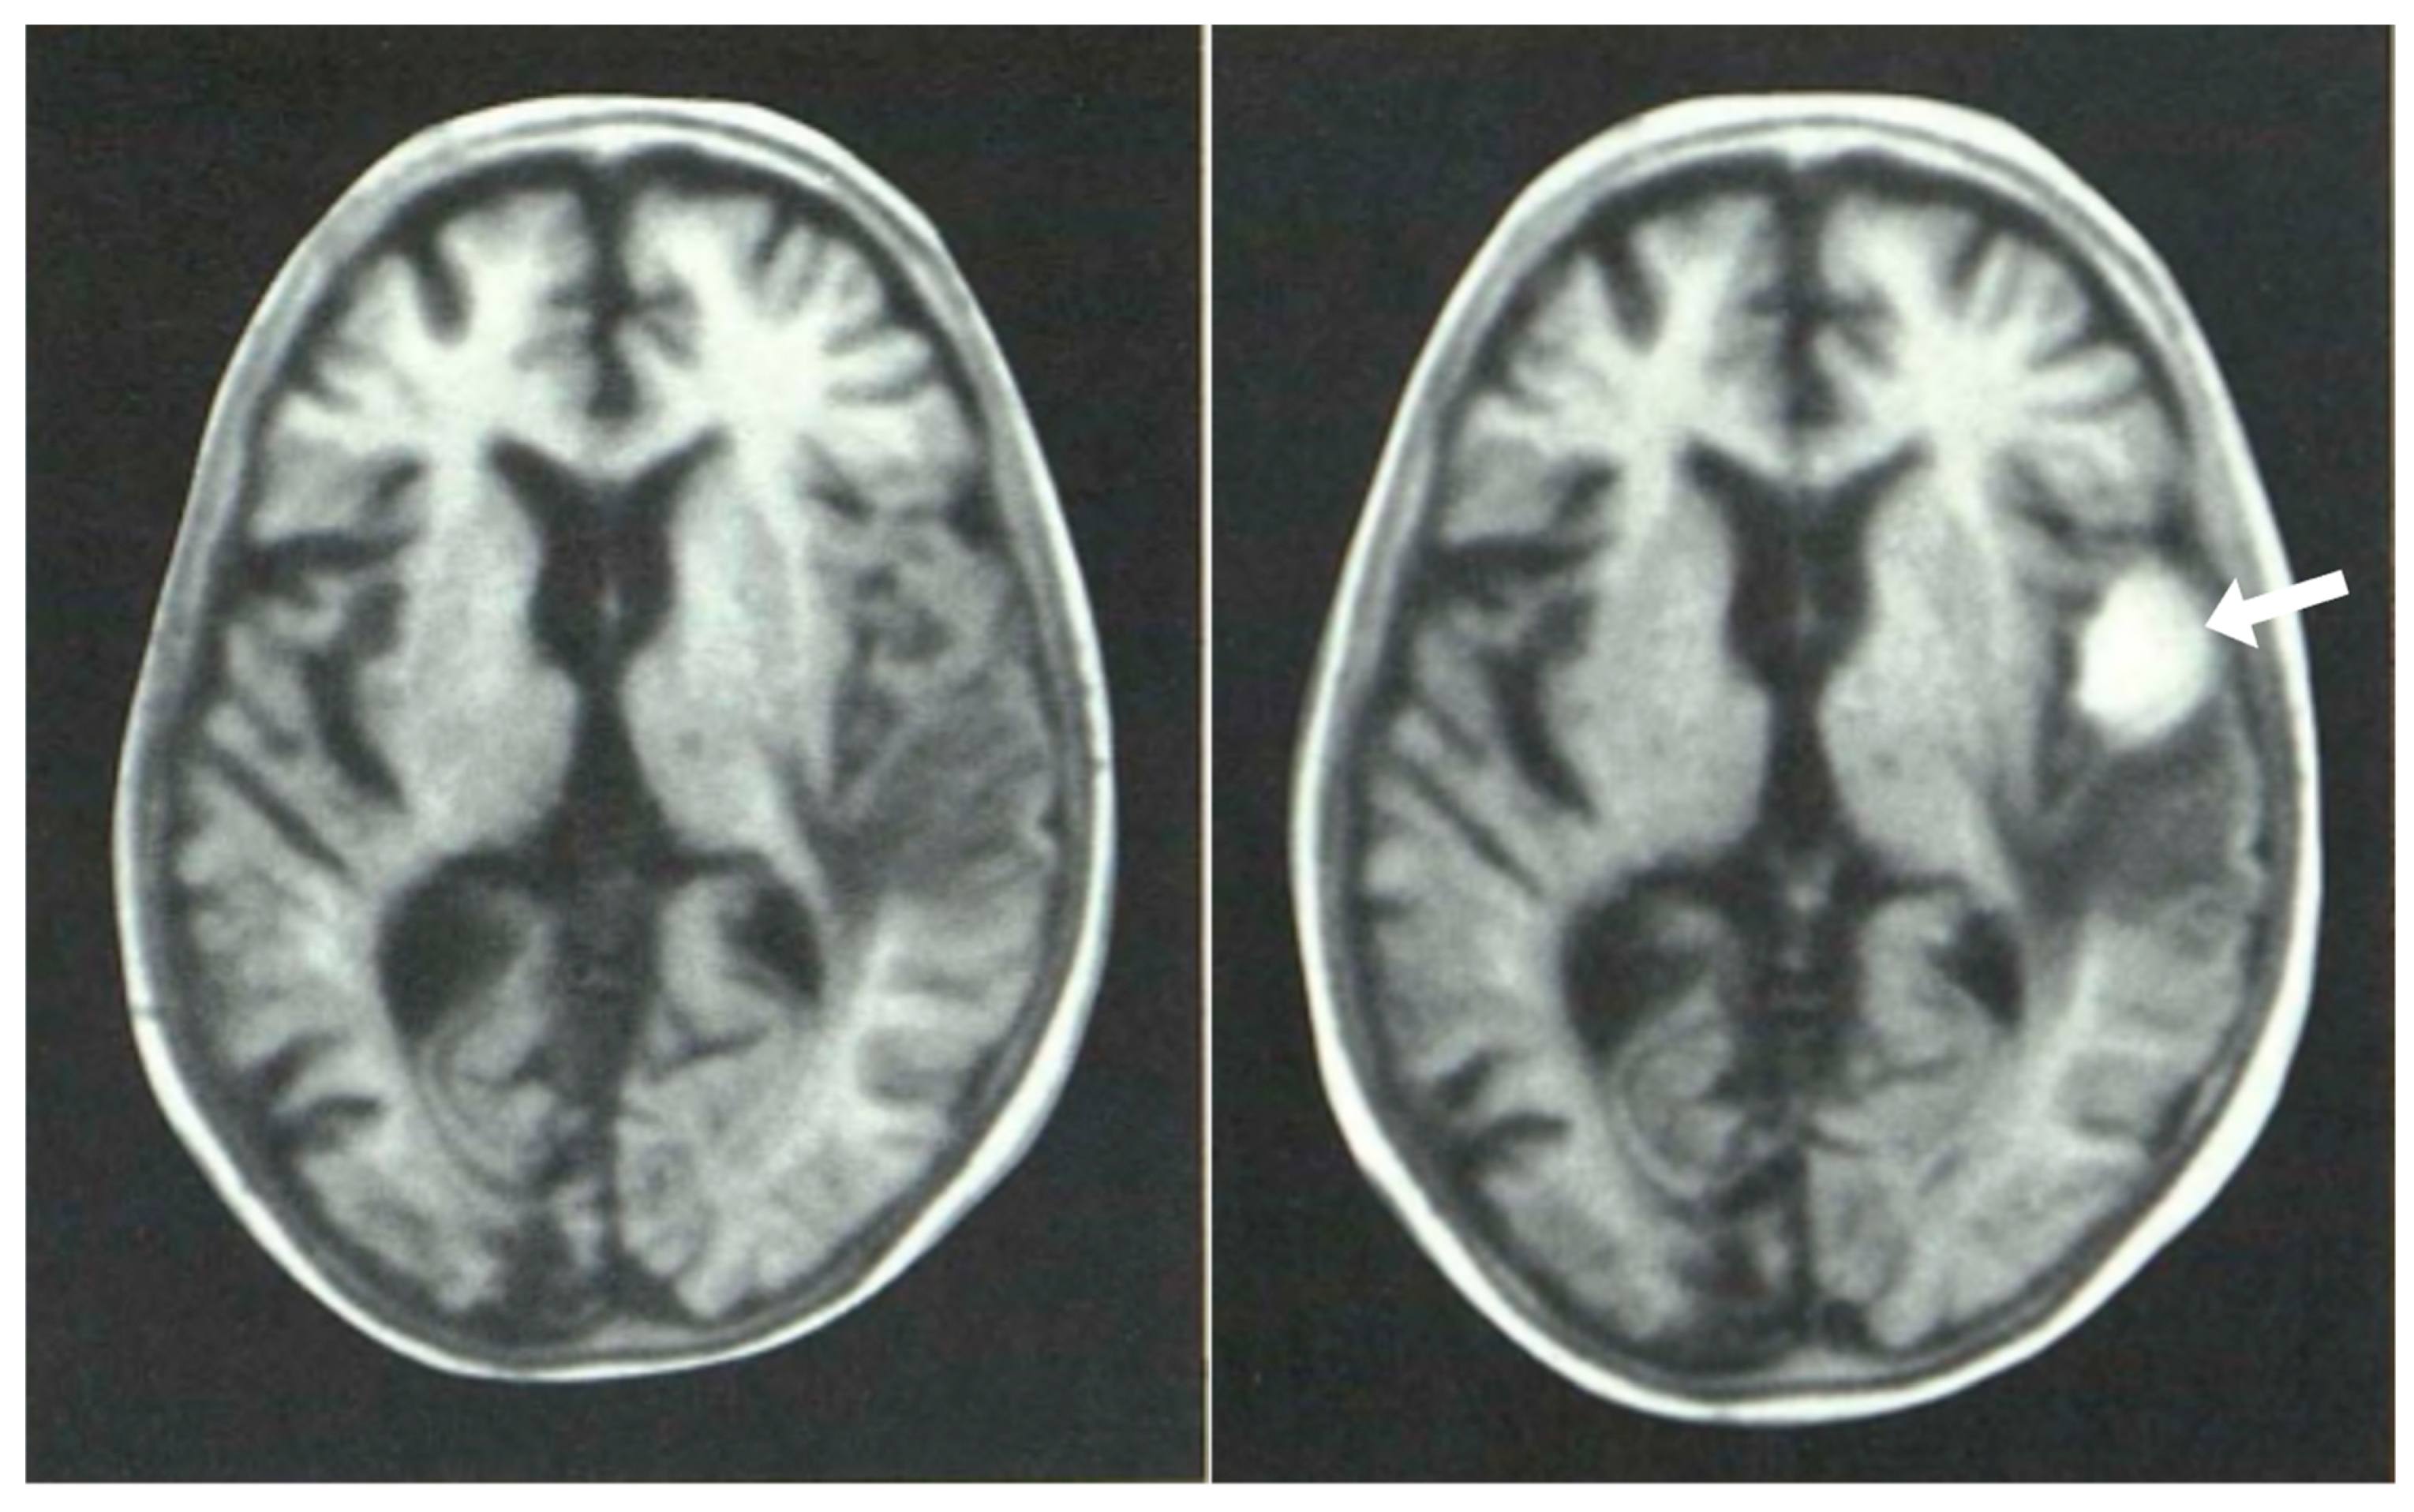

The second major revolution in soft tissue contrast imaging came in 1981. While CT had shown high soft tissue contrast in the brain and elsewhere relative to plain radiographs, it was possible to obtain even higher soft tissue contrast with magnetic resonance imaging (MRI). This was seen in ten cases of MS in which 19 lesions were depicted with CT but 112 more lesions were seen with MRI using T1 dependent inversion recovery (IR) sequences [7] (Figure 7). The additional lesions seen with MRI were smaller than those seen with CT and were demonstrated in white matter that appeared normal on CT. Even though MRI was much slower and of lower spatial resolution than CT, its superior soft tissue contrast resulted in a decisive advantage from a clinical point of view.

Figure 7.

Multiple sclerosis (MS): CT (left) and inversion recovery (IR) (right) (November 1981) [7]. Two larger lesions are seen on the CT image (left, arrows). These are also seen on the IR image (right, arrows). There are an additional six lesions seen in the periventricular white matter on the IR image (arrows). The additional lesions are seen in normal appearing white matter on the CT image.